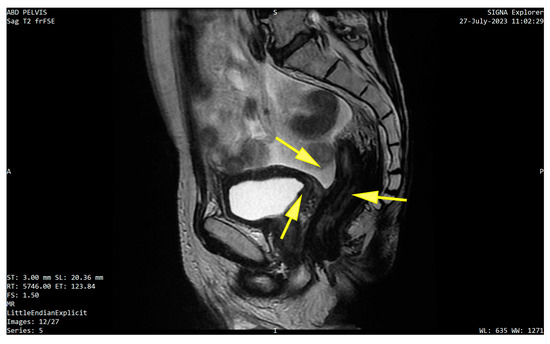

3. Detailed Case Description

| 25 | Present Case (2025) | 64/M | UCC G3/conventional and signet ring cell | GATA3, CK 20/CK5/6, P63, CDX | colonoscopy, rectal EUS TCB | rectal tenesmus, transit disorders (constipation/small volume diarrhea), moderate dysuria | DISTAL MEDIUM R |

| 25. | Present Case (2025) | 64/M | 0 | NO | Colostomy, NEOADJ CHT GC, RT | 15 M/D | T2N0M0 |